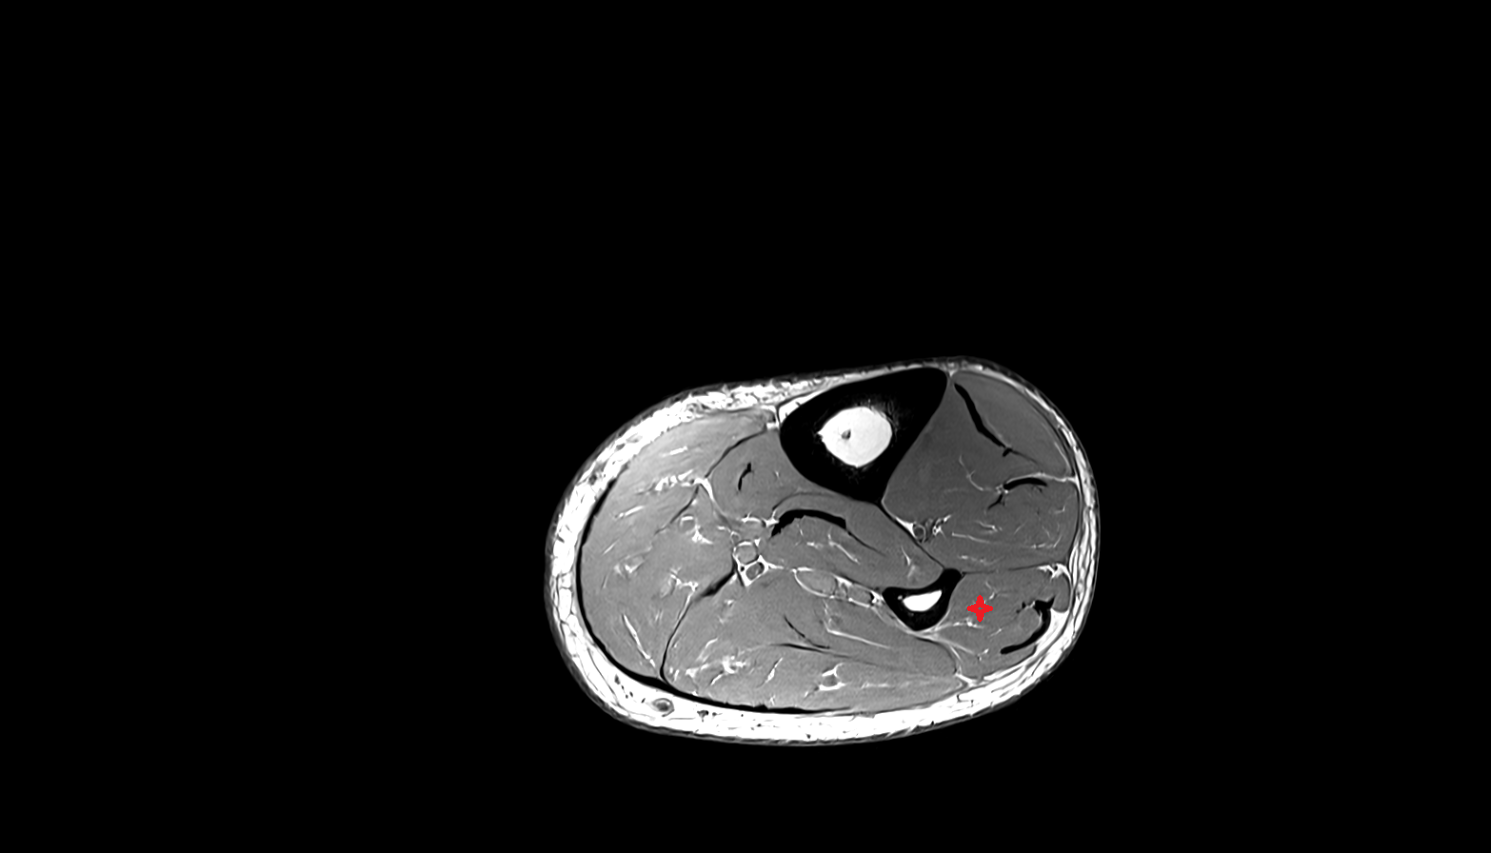

- Tibialis posterior muscle

- Flexor digitorum longus muscle

- Flexor hallucis longus muscle

- Tibialis posterior tendon

- Achilles tendon

- Hip joint